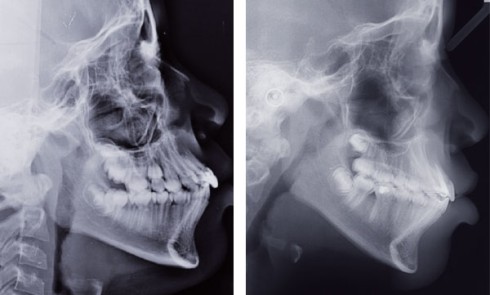

Article réservé à nos abonnés Extrusion orthodontique d’une incisive maxillaire

Situation clinique (fig. 1 à 9) Orlhane B., 10 ans, est adressée à l’unité fonctionnelle d’orthodontie de l’hôpital Bretonneau par son dentiste...